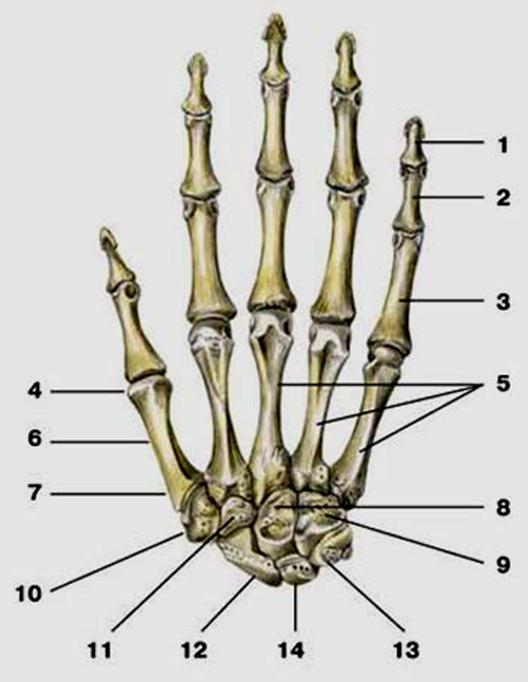

S: Числом 10 обозначена os ### (латинский язык).

S: Цифра 5 обозначает ossa ### (латинский язык).

S: Цифрой 8 обозначена os...

S: Числом 12 обозначена os...

S: Числом 13 обозначена os...

S: Цифра 3 указывает на...

S: Цифра 2 указывает на …

S: Цифра 1 указывает на....